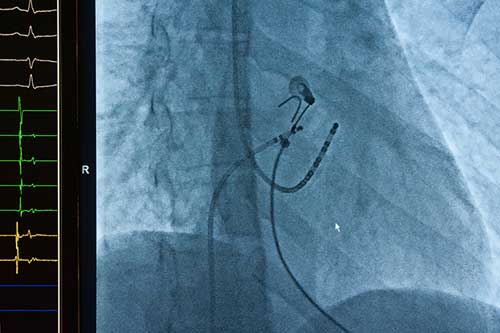

The plaintiff was a 54-year old man with a history of an irregular heart rhythm called atrial fibrillation. He underwent cardiac ablation for treatment of his condition. Cardiac ablation is a procedure in which catheters are inserted through a vein up into the heart. Multiple tools are utilized to localize the appropriate anatomy and target areas for ablation. Low energy is then delivered through the catheters to a targeted area outside the pulmonary veins (never deep within the pulmonary veins) to create a block so that electrical impulses originating from within the veins cannot propagate to the rest of the atrium and cause atrial fibrillation. Despite the first attempt at ablation, the plaintiff’s atrial fibrillation returned.

The plaintiff therefore underwent a repeat cardiac ablation on April 21, 2016. Following the plaintiff’s second ablation procedure, the plaintiff noted significant, progressive, and worsening difficulty breathing with minimal activity / shortness of breath, dizziness, and lightheadedness. A CT scan was performed that showed findings of pulmonary vein stenosis with severe stenosis on the right upper and left pulmonary veins. Plaintiff required a stenting procedure to try to improve his symptoms, but significant respiratory symptoms continued despite the stents. The plaintiff was not able to lead the active lifestyle he had previously enjoyed.

Plaintiff’s counsel obtained the mapping data from the 4/21/16 cardiac ablation and was prepared to present expert testimony that the defendant electrophysiologist who performed the procedure failed to appropriately identify targeted sites for ablation and negligently ablated deep into the pulmonary veins, resulting in severe pulmonary vein stenosis in all 4 pulmonary veins.